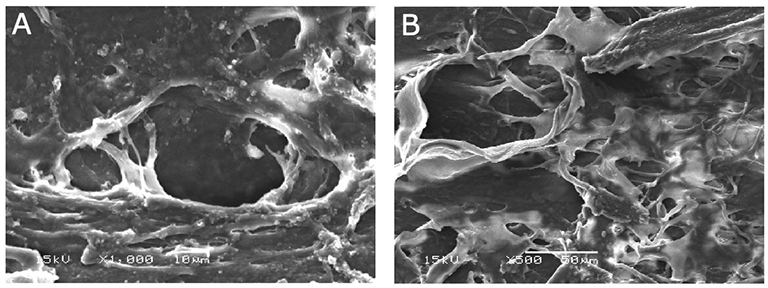

2. 섬유주소대(Trabecular meshwork, TM)의 직접적인 변화로,

레이저를 받으면 TM에 있는 내피세포가 소실되고 손상이 되면,

그 찌꺼기를 제거하려는 대식세포(Macrophage)의 기능이 증가되면서,

내부의 찌꺼기가 제거되면서 TM 내부의 공간이 넓어지면서 방수유출이 증가됩니다.

3. 섬유주소대(TM) 주변의 바탕질(Extracellular matrix, ECM)에서의 변화로,

소실된 섬유주 세포는 제거되고, 새로운 새포로 대체되게되는데,

이때 새롭게 생성된 세포는 기존의 세포와는 달리, 방수유출의 저항이 더 적은 새로운 ECM으로 대체된다고 알려져 있습니다.

이러한 ECM의 변화도 ALT의 기전 중의 하나로 알려져 있습니다.